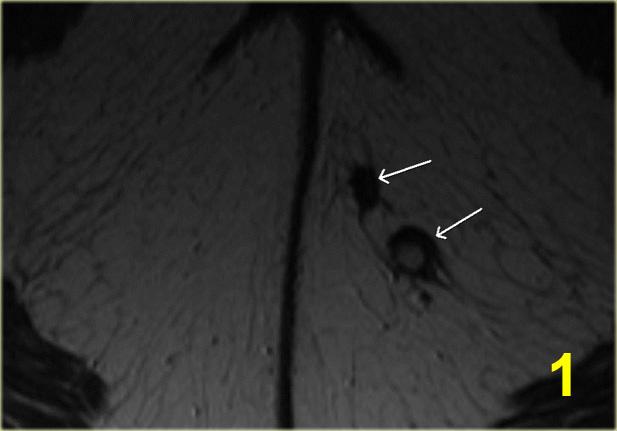

Bên trái là một ví dụ về rò phức tạp.

Hai đường rò ở mông trái hợp thành một đường rò duy nhất (số 1-2).

Đường rò này xuyên qua cơ thắt ngoài (số 4).

Trong khoang liên cơ thắt, đường rò lại phân chia thành hai nhánh (số 5).

Một nhánh kết thúc mù trong khoang liên cơ thắt (số 6).

Nhánh còn lại xuyên qua cơ thắt trong với khuyết niêm mạc ở vị trí 1 giờ.